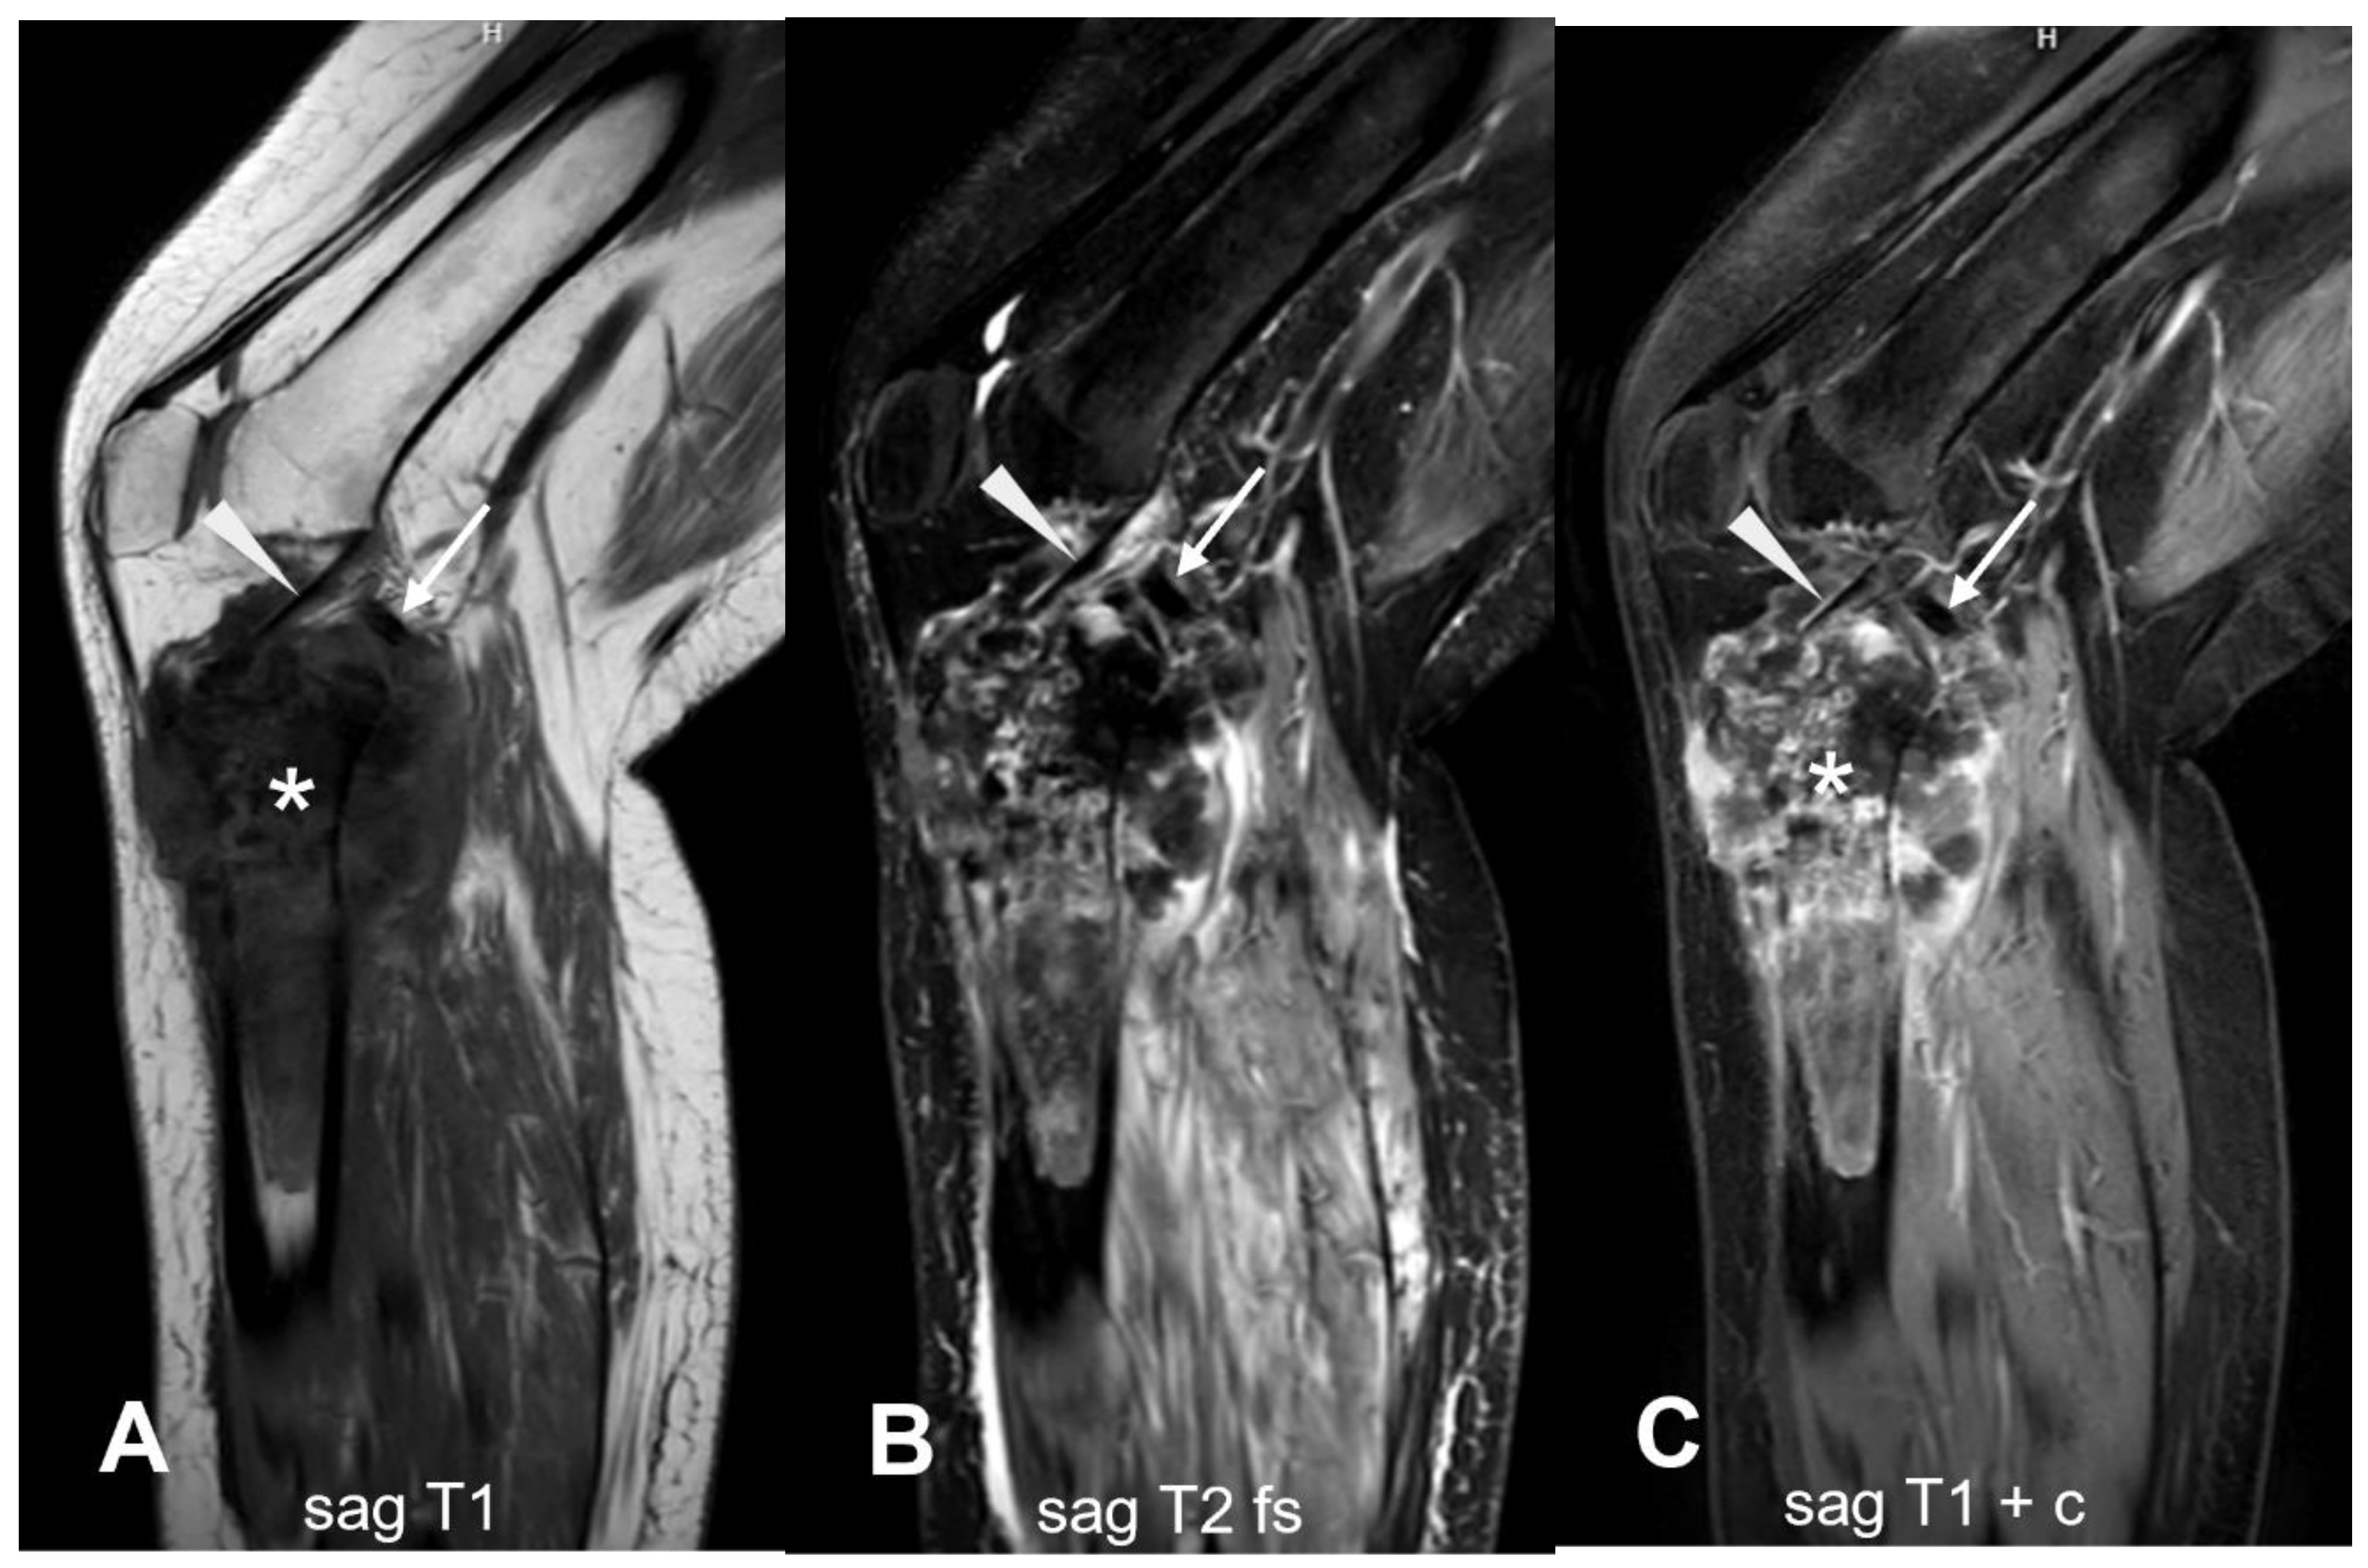

3.1.2. Secondary Osteosarcoma

3.2.2. Periosteal Osteosarcoma